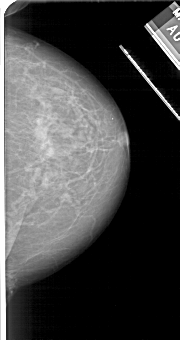

A_1112_1.LEFT_CC

LEFT_CC LINES 5191 PIXELS_PER_LINE 2416 BITS_PER_PIXEL 12 RESOLUTION 43.5 OVERLAY